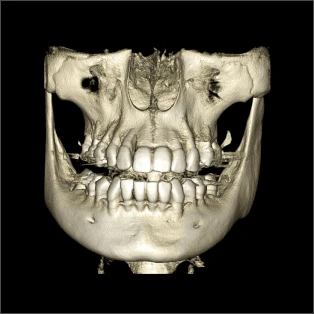

Один снимок — все детали

RAYSCAN 18х16 может с лёгкостью и точностью охватить обширную область анатомии. Его замечательная способность захватывать как назион, так и глабеллу, область от подбородка до лба, всё это в одном сканировании высотой 16 см действительно впечатляет.

Познакомьтесь с технологией получения изображений с использованием полноразмерного датчика от RAY. Этот метод не только позволяет получать объёмные изображения без сшивания, но и сводит к минимуму радиационное облучение в целях безопасности пациентов.